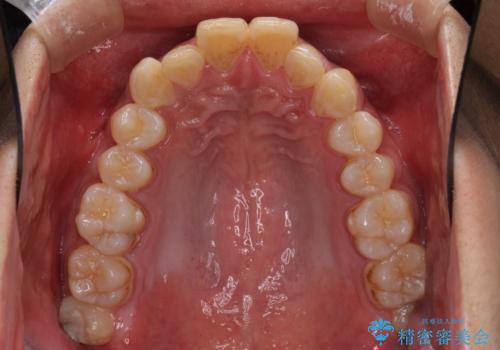

- 深い咬み合わせと前歯のデコボコを改善したいとのことで来院された患者様です。

口元の突出感はないものの、上顎前歯のデコボコが著しく、右側の咬み合わせがずれていたため、上顎右側第一小臼歯1本を抜歯することとしました。

咬合力が非常に強く、抜歯したスペースがなかなか閉じないであろうことは予想できましたが、思っていた以上に期間がかかりました。

前歯のすり減りも著しかったため、仕上げの位置の調整にも期間を要しました。